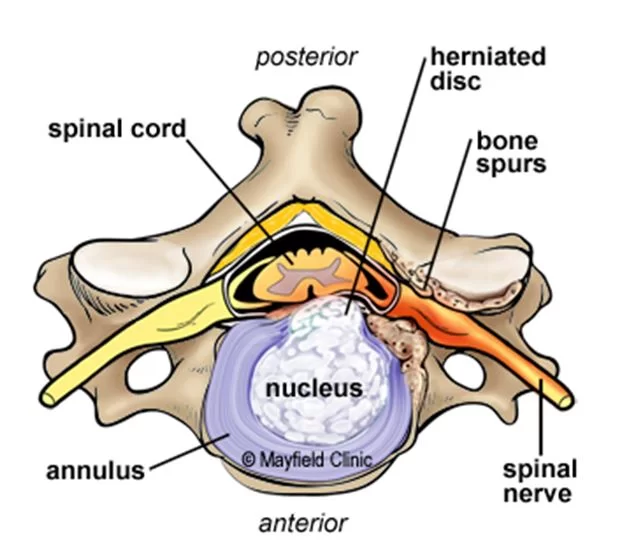

Η αυχενική δισκεκτομή είναι η χειρουργική επέμβαση κατά την οποία αφαιρείται ο σπασμένος ή εκφυλισμένος δίσκος ο οποίος πιέζει κάποιο νεύρο ή τον νωτιαίο μυελό (Εικόνα 1).

Η πρόσθια αυχενική δισκεκτομή γίνεται σε ασθενείς που έχουν δισκοκήλη/προβολή δίσκου ή/και οστεόφυτα στην αυχενική μοίρα της σπονδυλικής στήλης και ως εκ’ τούτου έχουν πόνο στον αυχένα και στα άνω άκρα.

Ο εκφυλισμός του δίσκου και των σπονδύλων (οστεόφυτα) μπορεί να επηρεάσουν το διαθέσιμο χώρο για το νωτιαίο μυελό και τα νεύρα. Ως αποτέλεσμα, ο νωτιαίος μυελός και τα νεύρα ενδέχεται να συμπιεστούν ή και να τραυματιστούν.